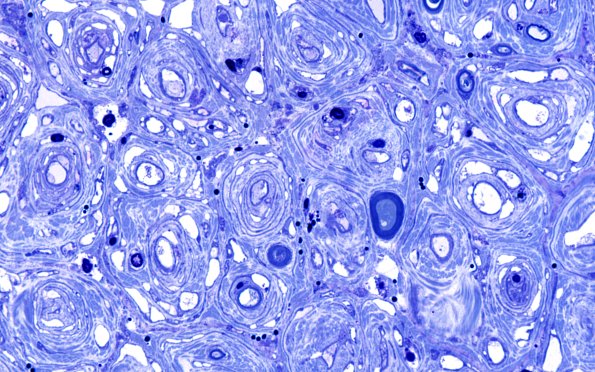

8F5 CIDP (Case 8) Roots Plastic 40X 10

There are numerous onion bulbs and demyelinated axons in this biopsy of one of the expanded roots. (Plastic sections)